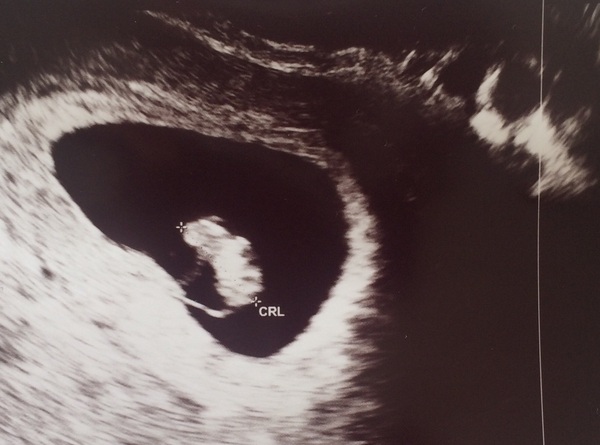

I had my early scan yesterday, and all looks well! I was pretty worried as I had a week of pretty bad cramps. Sizing confirmed 7 w +1 and could see the little heartbeat flickering.

Feeling a lot better now the cramping is easing off, nausea on its own seems easier to deal with (although it's still pretty grim).